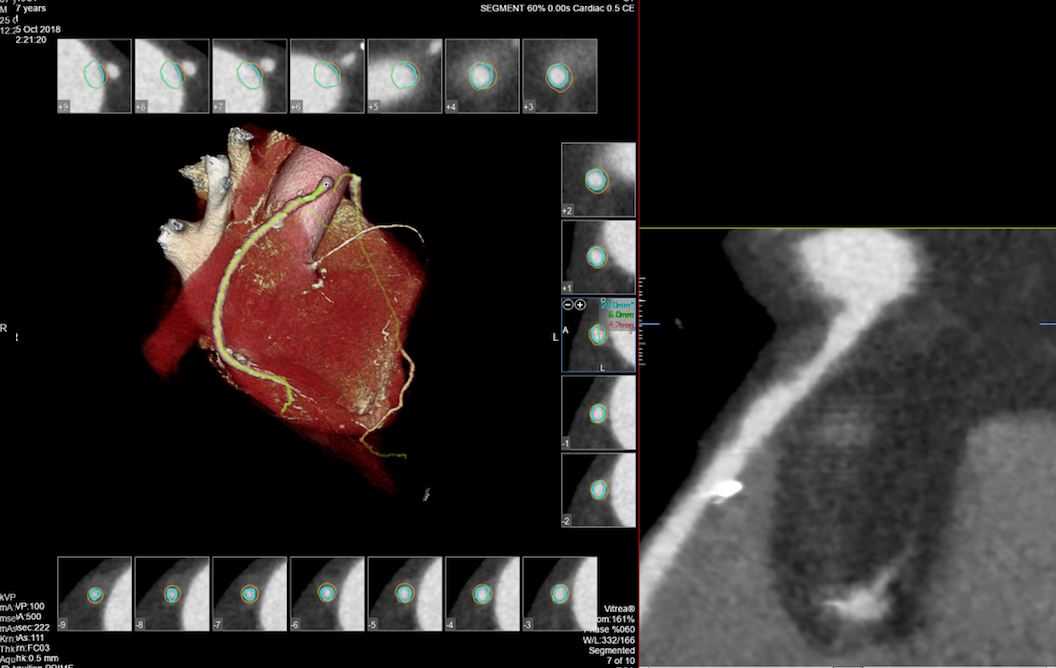

- MSCT koronarografija (prikaz krvnih žila srca CT-om, bez neugodnosti i komplikacija koje nosi klasična koronarografija), u saradnji s Poliklinkom dr.Al-Tawil